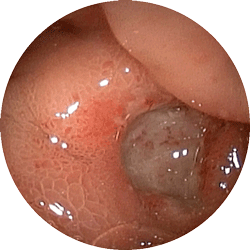

胃潰瘍

食欲不振で来院

内服薬1ヶ月で治癒